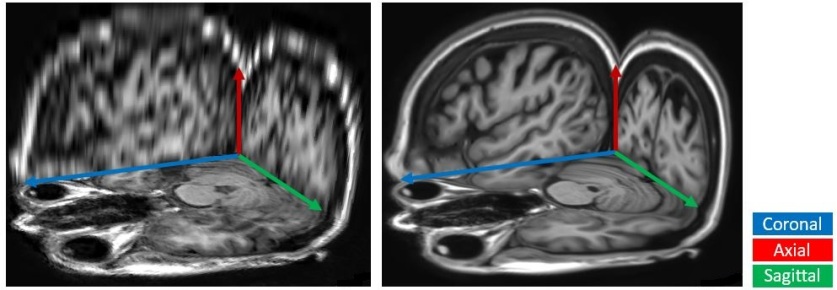

In practice, most MR volumes are taken anisotropically with a high resolution within slices and a sparse resolution between slices. For example, Fig. 1 shows a brain MR scan whose axial direction is sparsely sampled. As a result, image quality suffers when viewing from coronal and sagittal directions.

Figure 1: The axial, coronal, and sagittal views of an anisotropic MR volume are fitted to isotropic resolution through (Left) linear interpolation and (Right) our proposed slice-interpolation method.